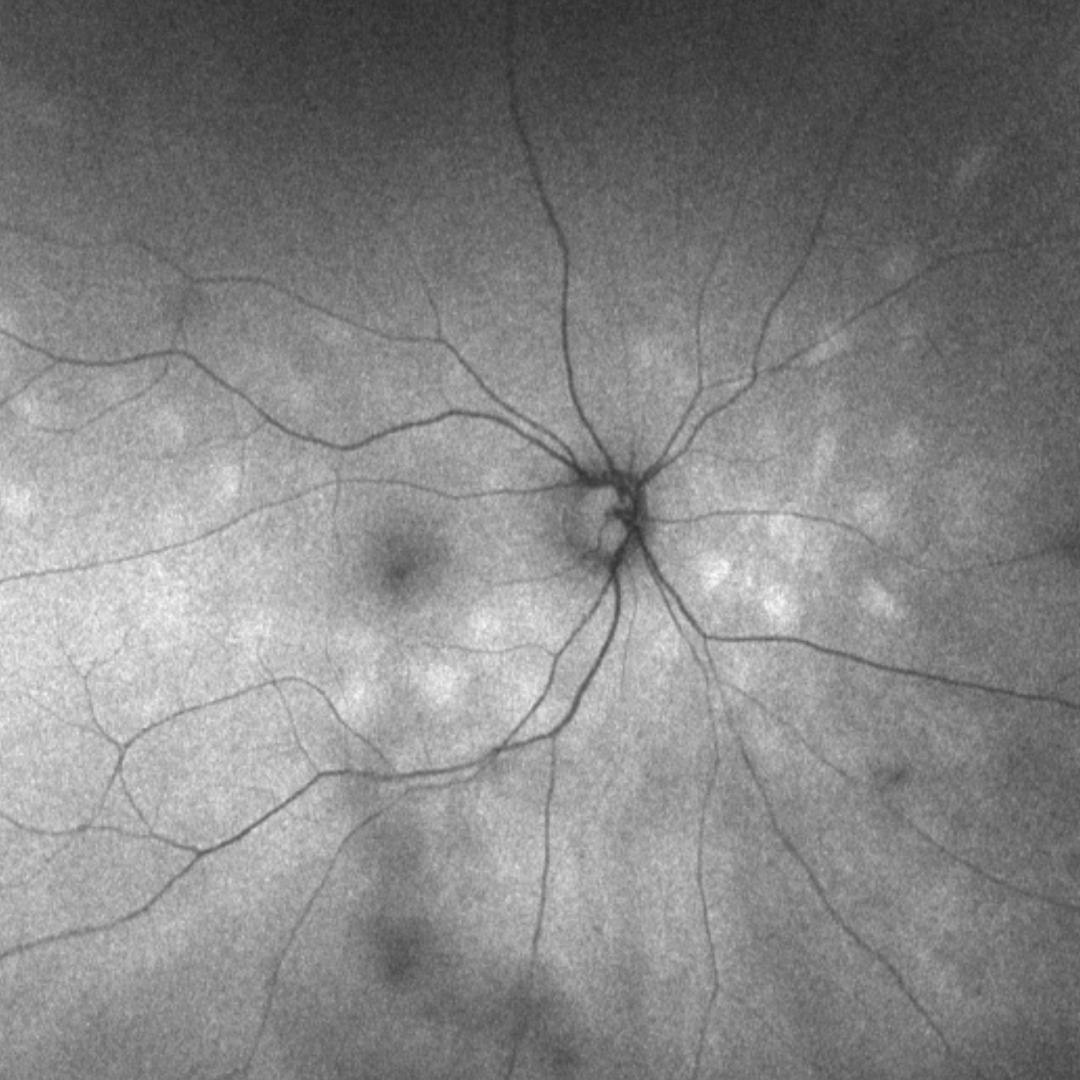

The spectrum of white dot syndromes are characterised by hypopigmented inflammatory lesions of the outer retina, RPE, choriocapillaris and/or choroid.

White dot syndromes have associated symptoms of blurred vision, floaters, photopsias, and scotoma and some also show retinal and/or vitreal signs of inflammation. Multimodal imaging is useful in distinguishing between the disease identities within the group of white dot syndromes.

Within this resource, we will explore the key white dot syndromes and illustrate the clinical characteristics of each using multimodal imaging.